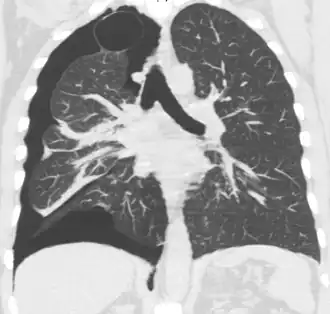

Computed tomography

CT with the identification of underlying lung lesion: an apical bulla on the right side

A CT scan is not necessary for the diagnosis of pneumothorax, but it can be useful in particular situations. In some lung diseases, especially emphysema, it is possible for abnormal lung areas such as bullae (large air-filled sacs) to have the same appearance as a pneumothorax on chest X-ray, and it may not be safe to apply any treatment before the distinction is made and before the exact location and size of the pneumothorax is determined.[18] In trauma, where it may not be possible to perform an upright film, chest radiography may miss up to a third of pneumothoraces, while CT remains very sensitive.[21]

A further use of CT is in the identification of underlying lung lesions. In presumed primary pneumothorax, it may help to identify blebs or cystic lesions (in anticipation of treatment, see below), and in secondary pneumothorax, it can help to identify most of the causes listed above.[18][22]